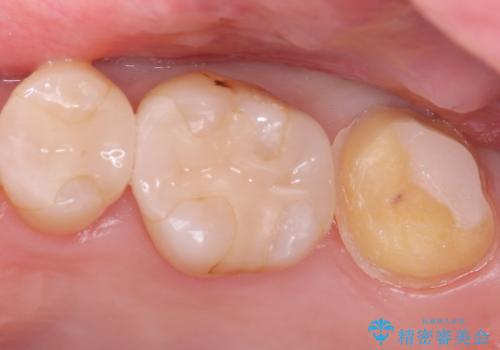

【セラミッククラウン】インレーの下の大きな虫歯

- レントゲンにて昔入れたインレーの下に虫歯が見つかった患者様です。

歯髄に近接する虫歯でしたが、根管治療は必要なくクラウンにて修復を行うことができました。